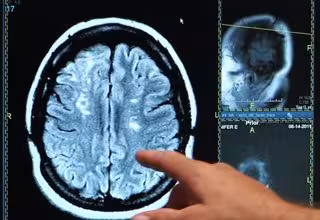

Ictus, derrame cerebral, cerebro

ONALD REAGAN UCLA MEDICAL CENTER - Archivo